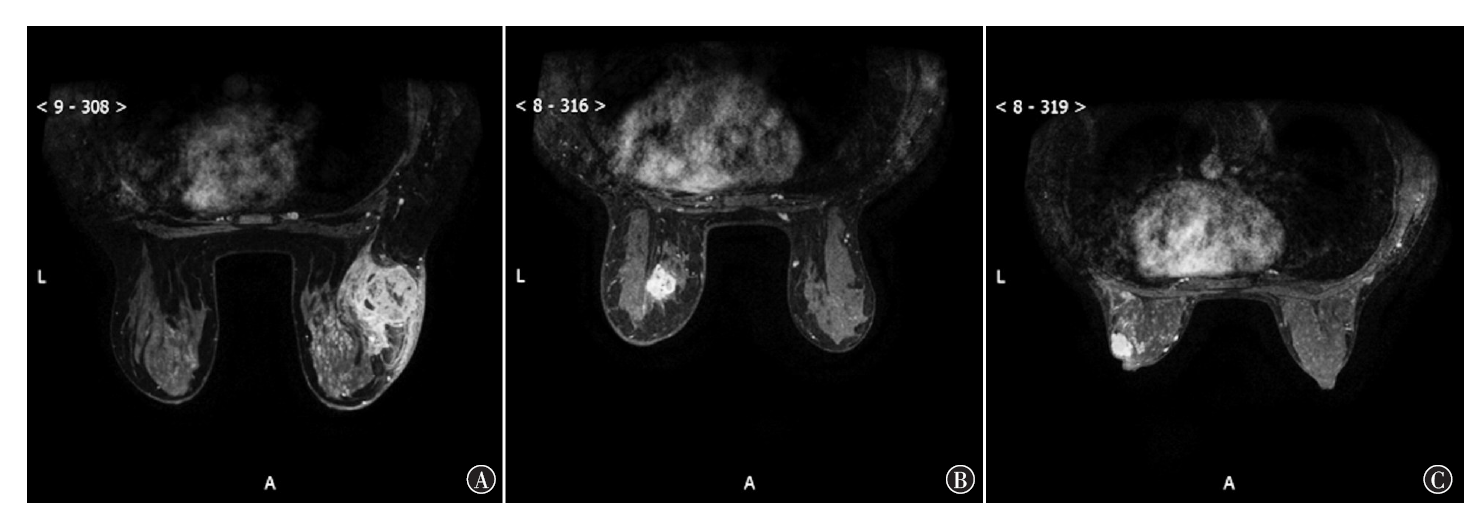

目的 探讨基于多模态MRI特征构建的预测模型用于乳腺影像报告和数据系统(BI-RADS)4类乳腺肿瘤良恶性的鉴别诊断价值。方法 回顾性纳入2018年1月—2023年1月于三二〇一医院行对比增强MRI检查证实为BI-RADS 4类乳腺肿瘤的患者204例,根据手术后病理组织学检查结果分为恶性组(124例)和良性组(80例),比较两组临床及MRI影像学特征资料;对BI-RADS 4类乳腺肿瘤良恶性鉴别诊断指标进行多因素logistic回归分析;构建BI-RADS 4类乳腺肿瘤良恶性鉴别诊断预测模型;采用受试者操作特征(ROC)曲线比较各指标对BI-RADS 4类乳腺肿瘤良恶性的鉴别诊断价值。结果 恶性组和良性组年龄(t=7.78,P<0.001)、内部强化类型(χ2=14.50,P=0.002)、表观弥散系数(t=-6.77,P<0.001)、纵向弛豫时间(T1)值(t=-6.15,P<0.001)、纵向弛豫率(R1)值(t=7.02,P<0.001)差异均具有统计学意义。多因素分析显示,年龄(OR=1.16,95%CI为1.07~1.25,P<0.001)、内部强化类型(不均匀:OR=8.08,95%CI为2.21~29.51,P=0.002)、表观弥散系数(OR=0.01,95%CI为0.00~0.05,P<0.001)、T1值(OR=0.99,95%CI为0.99~1.00,P<0.001)及R1值(OR=1 043.50,95%CI为46.48~23 426.36,P<0.001)均是BI-RADS 4类乳腺肿瘤良恶性鉴别诊断的独立影响因素。依据多因素分析结果构建BI-RADS 4类乳腺肿瘤良恶性鉴别诊断的logistic回归模型,logit(P)=0.05+0.15×年龄+2.09×内部强化类型-5.21×表观弥散系数-0.01×T1值+6.95×R1值。ROC曲线分析显示,利用年龄、内部强化类型、表观弥散系数、T1 值、R1值、logistic回归模型P值对于乳腺肿瘤良恶性进行鉴别诊断,约登指数分别为40.60%、39.68%、49.44%、38.23%、43.27%、75.70%,ROC曲线下面积分别为0.757、0.647、0.718、0.724、0.757、0.924。结论 内部强化类型、表观弥散系数、T1值及R1值在内的多模态磁共振指标均可用于BI-RADS 4类乳腺肿瘤良恶性的鉴别诊断,基于上述指标构建的鉴别诊断模型对BI-RADS 4类乳腺肿瘤良恶性具有良好的鉴别诊断效能。

Objective To explore the value of the prediction model based on multimodal MRI characteristics for the differential diagnosis of benign and malignant breast tumors of breast imaging reporting and date system (BI-RADS) 4 types. Methods A total of 204 patients with BI-RADS 4 types of breast tumors confirmed by contrast-enhanced MRI in 3201 Hospital from January 2018 to January 2023 were retrospectively included, and were divided into the malignant group (124 cases) and the benign group (80 cases) according to surgical histopathology. Clinical and MRI imaging characteristics of the two groups were compared. Multivariate logistic regression analysis was performed for the differential diagnosis indexes of benign and malignant breast tumors of BI-RADS 4 types. A prediction model for differential diagnosis of benign and malignant BI-RADS 4 types of breast tumors was constructed. Receiver operator characteristic (ROC) curve was used to compare the differential diagnostic value of each index for benign and malignant BI-RADS 4 types of breast tumors. Results There were statistically significant differences in age (t=7.78, P<0.001), internal enhancement type (χ2=14.50, P=0.002), apparent diffusion coefficient (t=-6.77, P<0.001) longitudinal relaxation time (T1) value (t=-6.15, P<0.001), and longitudinal relaxation rate (R1) value (t=7.02, P<0.001) between the malignant and benign groups. Multivariate analysis showed that age (OR=1.16, 95%CI: 1.07-1.25, P<0.001), internal reinforcement type (uneven: OR=8.08, 95%CI: 2.21-29.51, P=0.002), apparent diffusion coefficient (OR=0.01, 95%CI: 0.00-0.05, P<0.001), T1 value (OR=0.99, 95%CI: 0.99-1.00, P<0.001), and R1 value (OR=1 043.50, 95%CI: 46.48-2 3426.36, P<0.001) were all independent factors influencing the differential diagnosis of benign and malignant BI-RADS 4 types of breast tumors. According to the results of multivariate analysis, a logistic regression model for differential diagnosis of benign and malignant BI-RADS 4 types of breast tumors was constructed. logit (P)=0.05+0.15×age+2.09×internal enhancement type-5.21×apparent diffusion coefficient-0.01×T1 value+6.95×R1 value. ROC curve analysis showed that age, internal reinforcement type, apparent diffusion coefficient, T1 value, R1 value, and logistic regression model P-value were used for differential diagnosis of benign and malignant breast tumors, the Jordan indexes were 40.60%, 39.68%, 49.44%, 38.23%, 43.27%, and 75.70%, respectively. The areas under the ROC curve were 0.757, 0.647, 0.718, 0.724, 0.757, and 0.924, respectively. Conclusion Multimodal magnetic resonance indexes, including internal reinforcement type, apparent diffusion coefficient, T1 value and R1 value, can be used for the differential diagnosis of benign and malignant BI-RADS 4 types of breast tumors. The differential diagnostic model based on the above indexes has good differential diagnostic efficacy for benign and malignant BI-RADS 4 types of breast tumors.